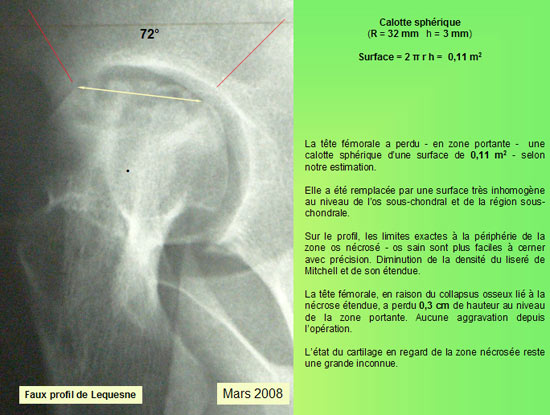

MESURE DE LA SURFACE

Sur le plan radiographique : - La zone nécrotique est nettoyée. - L'aplatissement de la tête fémorale ne s'est pas aggravé depuis l'intervention. - le corail naturel est résorbé au niveau du col ; il est partiellement résorbé au niveau de la tête fémorale.